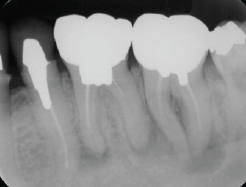

<臼歯部の感染根管治療終了後の14枚法>

(図20)

術前には数歯に根尖病変を疑う透過像が確認できたが

術後改善傾向にあることが確認できる